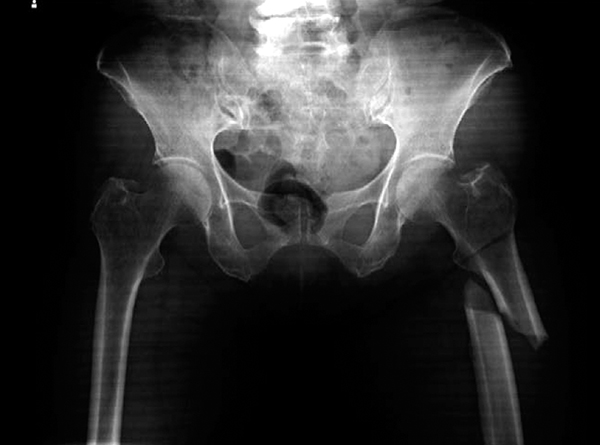

75歳の女性.交通事故により受傷.救急搬送時のエックス線写真を下に示す.遠位骨片を短縮転位させる

- 1.中殿筋

- 2.小殿筋

- 3.腸腰筋

- 4.上双子筋

- 5.大腿直筋